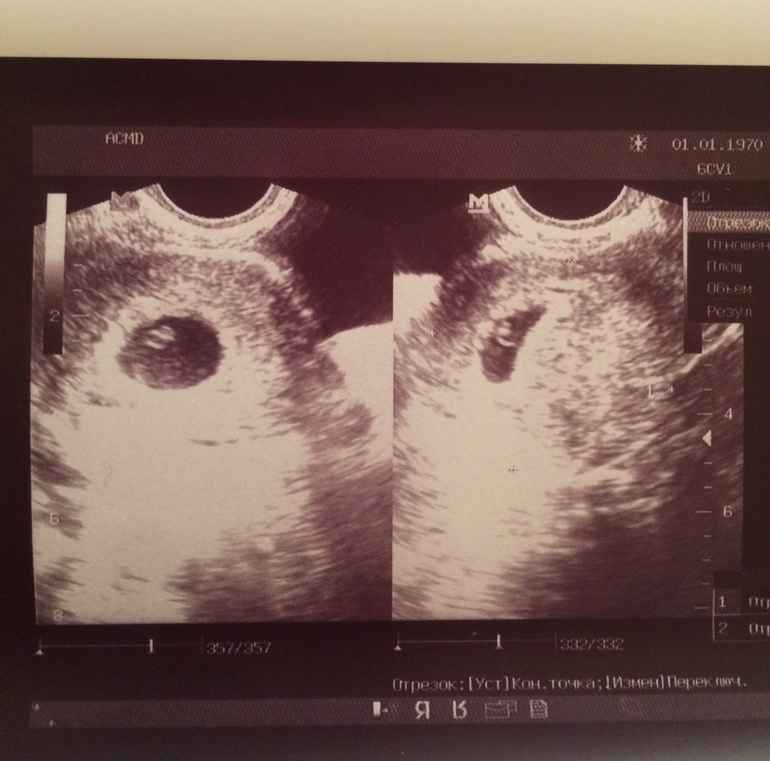

Это наше первое узи, в 5 недель и 6 дней акушерских.

Смущает что ПЯ 18 мм соответсвует сроку 6-7 недель а КТР 3,5 мм на 4-5 недель. Это нормально? Сердцебиение есть , не слушали но доктор сказала что есть.